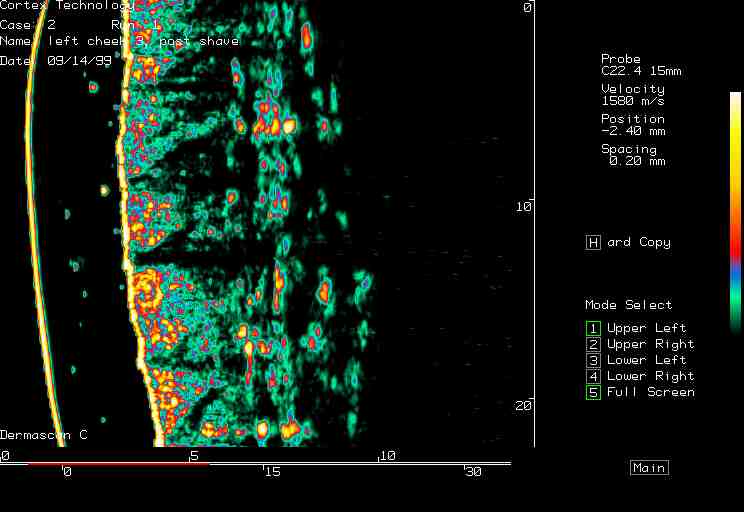

| Shaving reactions |  Cheek, prior to shaving |

Cheek, 0 min post shaving |

Cheek, 90 min post shaving |